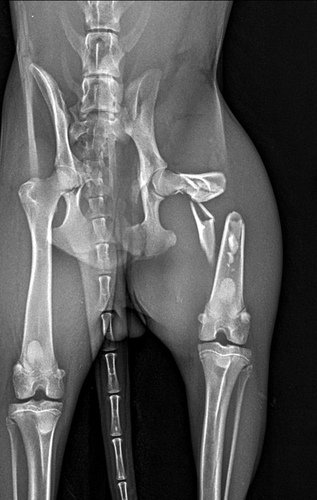

O animal tinha sido atropelado na noite anterior e já estava no local a mais de 15h! Como era caminho para o Natã, ele parou pra ver o que poderia ser feito e viu que o animal estava bem debilitado. Com a ajuda da concessionária que administra a rodovia, levou o animal para uma clínica particular em São José e após exames foram encontradas diversas fraturas e também o rompimento da bexiga.

Como nenhum empreendimento de fauna (Selva Viva e CRAS Univap) quis receber o animal no estado que se encontrava e as cirurgias precisavam ser feitas em caráter emergencial, o animal foi operado com a ajuda dos veterinários Henrique (Clínica VetBio) e Vanessa (Clínica Ortocanis). Estamos organizando essa vaquinha para cobrir os custos da cirurgia na bexiga, cirurgias ortopédicas, internação, medicamentos e alimentação do animal até que possa ser encaminhado para o CETAS de Lorena (que aceitou receber o animal depois que estivesse com a saúde estabilizada, já que, não tinha condições de arcar com as despesas médicas do animal).